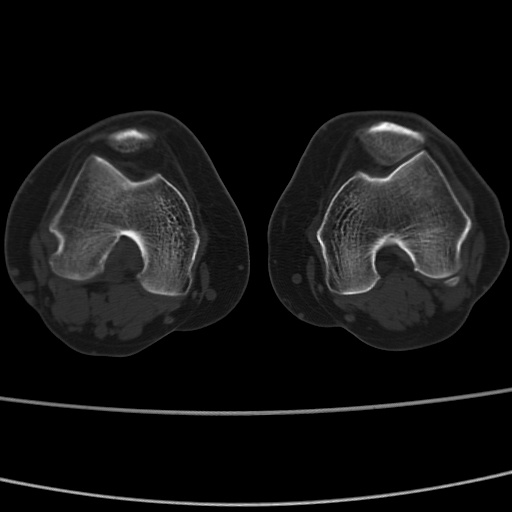

女性,50岁。【请提供患者临床症状体征】

右膝关节退行性改变,关节游离鼠。

右膝关节退行性改变,滑膜黏液囊钙/骨化并游离。